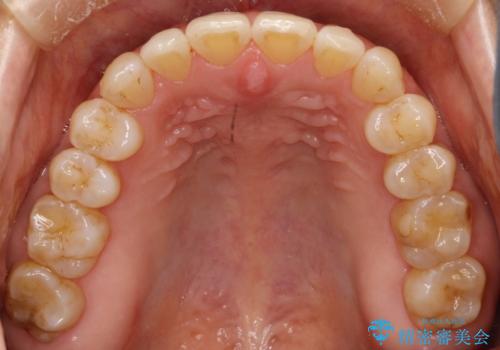

前歯の隙間 インビザラインによる目立たない成人矯正

- 前歯の隙間を気にされて来院されました。

インビザラインにて、目立たずに矯正治療を行うこととしました。

歯と歯の間にある隙間を閉じるのは、インビザラインでもしっかり治療できます。